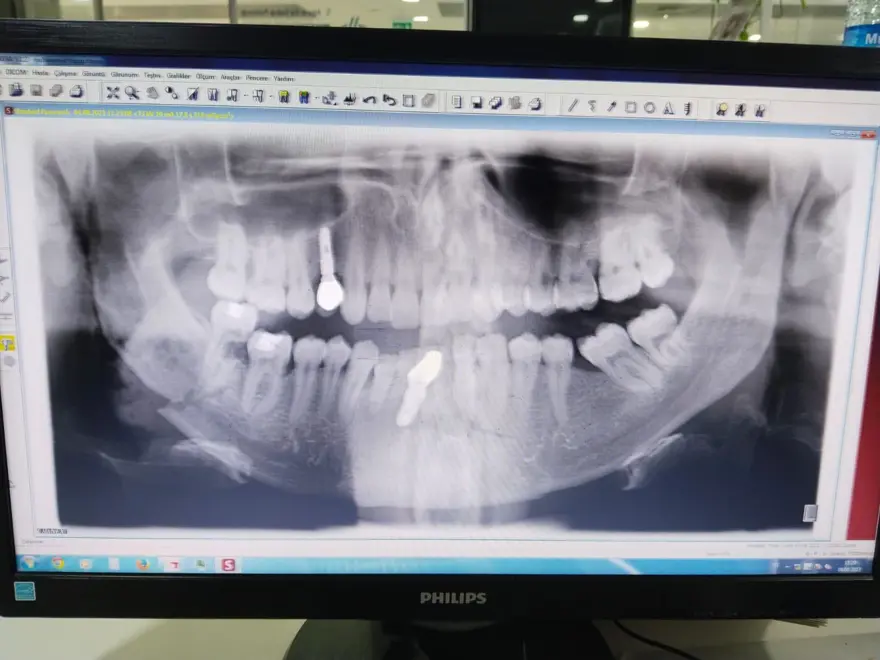

Çenesi ve vücudunun çeşitli yerlerinde kırıklar oluşan Topçu, Yıldızeli Devlet Hastanesi’ndeki müdahalenin ardından Sivas’ta özel bir hastaneye sevk edildi.